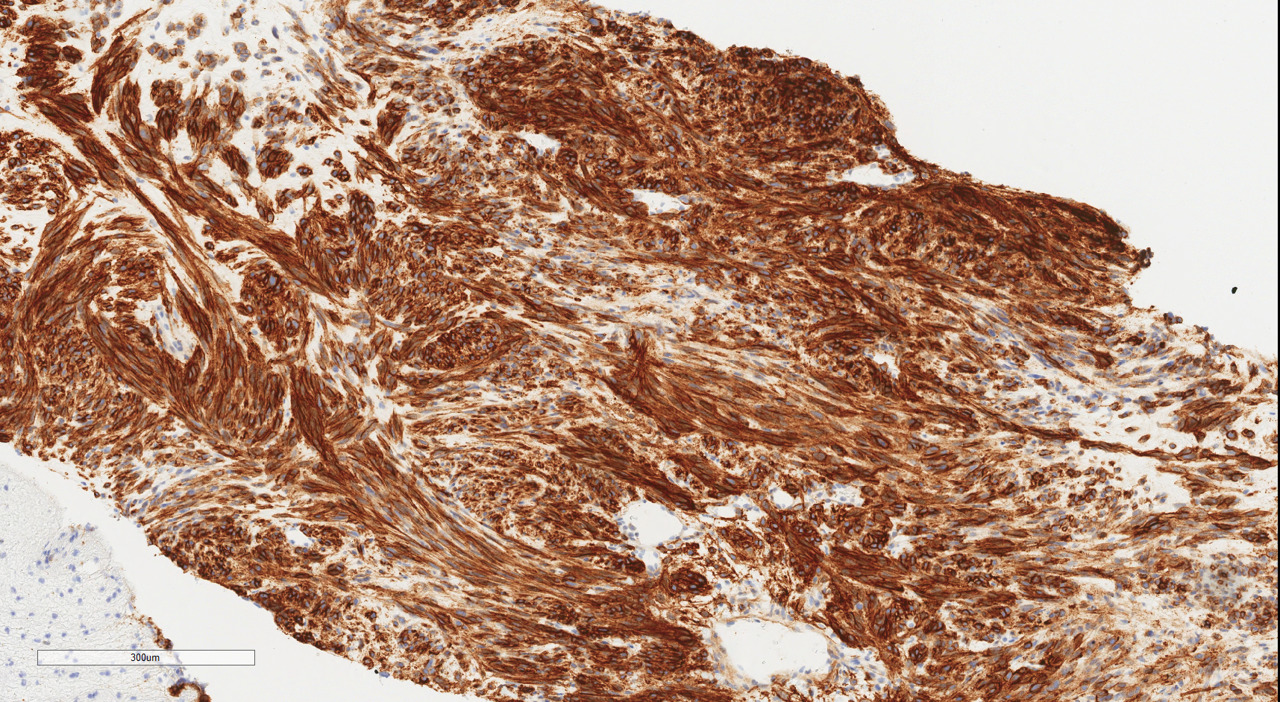

The patient was discharged home on postpartum day seven. At her surgical oncology appointment four weeks later, she continued to show signs of malnutrition with a weight loss of 20 kg compared to her intrapartum weight. An ultrasound-guided biopsy of her retroperitoneal mass confirmed the diagnosis of GIST with spindled morphology and multiple liver metastases (Figures 4 and 5). The patient’s case was reviewed in a multidisciplinary gastrointestinal tumor board, where neoadjuvant imatinib therapy was recommended. At her follow-up visit, the patient reported an increased appetite, and the size of her abdominal wall mass had decreased by approximately half. Due to an excellent initial response to imatinib therapy, this was to be continued with imaging at three-month intervals to assess her disease status; however, this plan was complicated by the SARS-CoV-2 pandemic, as the patient traveled oversees and was unable to return for several months. She did continue to take imatinib without difficulty during this time period.